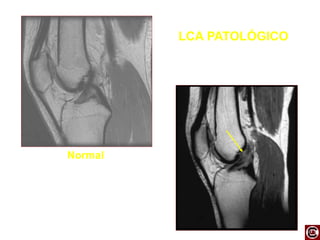

LCA PATOLÓGICO

Normal

LIGAMENTO CRUZADO ANTERIOR-DP